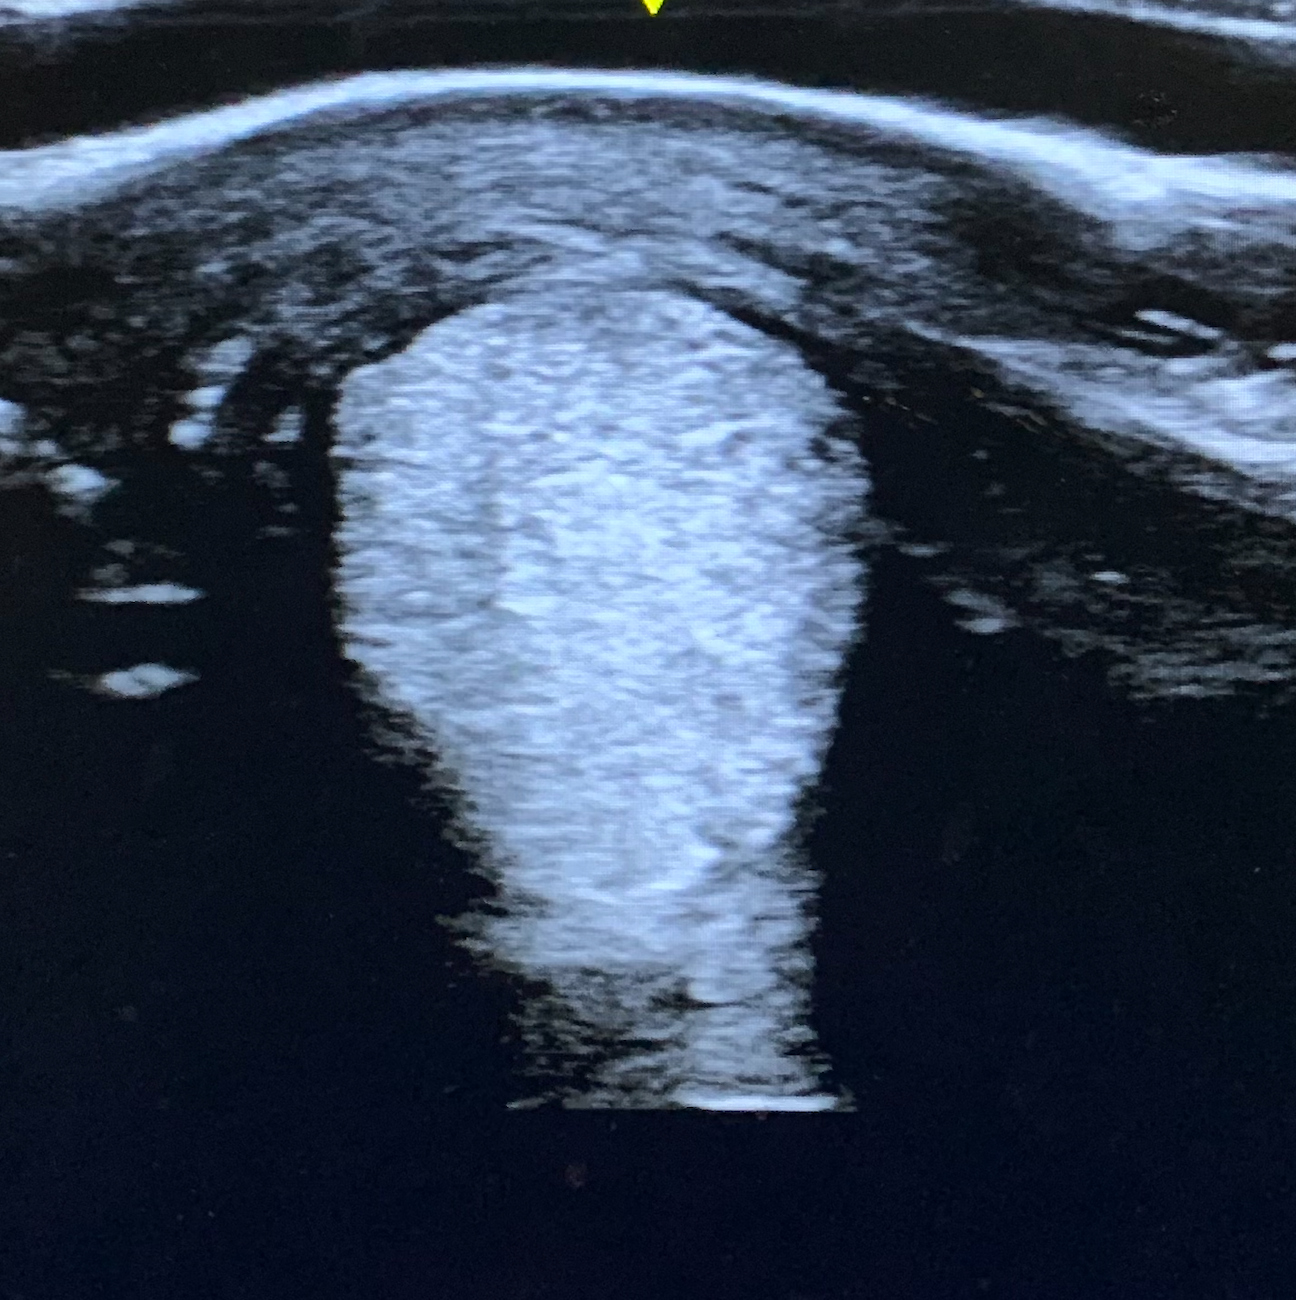

Verletzung des Fesselträgerschenkels

Grand Prix Dressurpferd

Die nachfolgenden Bilder zeigen den Heilungsverlauf eines Pferdes mit einer schwerwiegenden Verletzung des Fesselträgerschenkels mit ca. 60% Schädigung. Diese Verletzung bedeutet in vielen Fällen das Ende der Sportkarriere. Das Pferd wurde mit Stoßwellentherapie, PRP und Wachstumsfaktoren behandelt. Nach ca. 3 Monaten war das Pferd wieder lahmfrei und konnte im gleichen Jahr in den Sport zurückkehren.